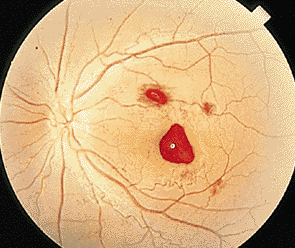

对于很多患者而言,玻璃体变性主要原因就是随着年龄不断增加,新陈代谢不断变缓,使得玻璃体自身变性。比如像星状玻璃体变性,常常见于50岁以上,不过它只是引起视力的不适,并不会导致视力下降。因为玻璃体内新陈代谢缓慢,而出现了含钙的脂质白色小球。而玻璃体变性中更为严重的是出现液化现象,特别是闪辉性玻璃体液化,由于严重眼外伤和手术后眼内出血导致的玻璃体或前房会出现无数黄白色和其他颜色的胆固醇结晶。

对于玻璃体混浊这样复杂的症状,一般的眼科医院无法根治,由于眼睛玻璃体的特殊性,目前尚无有玻璃体变性的特效药,只能经过长期的治疗和巩固,使得玻璃体不会出现其他病变。所以对于病情较为严重的玻璃体变性患者而言,就像因为变性引发的视网膜剥离或玻璃体出血等等,这些会出现视力严重减退,眼睛发红、疼痛、畏光等等,一定要到专业的眼科医院进行医治,比如在厦门眼科医院的眼底专科,常年来除了眼底病之外,玻璃体变性治疗领域在全国也是处于领先位置。